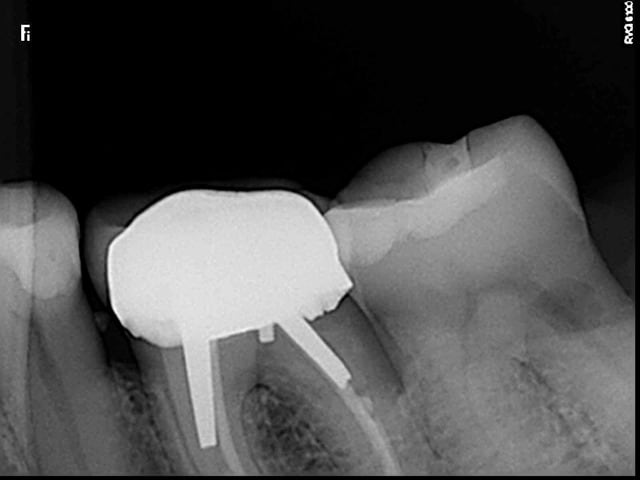

Bonjour, la patiente présente les signes d'une pulpite débutante sur 37 et à la radio j'ai trouvé çà : une lacune (érosion interne?) de forme atypique...j'ai pris plusieurs clichés avec angulations différentes.

Quelqu'un sait il ce que c'est ? Le diagnostic ? J'envisage le TC, des précautions particulières ?

Entre la première et la deuxième radio, tu as clairement un décalage de la lésion.

De plus les contours du canal distal sont très nets sur toutes les radios

On devine une résorption osseuse sur cette racine distale

Donc pour moi tout indique que c'est externe

Même si je n'en suis pas certain à 100%. On voit bien le canal distal défini en effet derrière la lésion de résorption. Après je pense que les clichés sont décalés ne le sont pas assez pour se faire une meilleure idée mais il semble que la lésion soit décalée entre les clichés 1 et 2 par rapport au canal donc externe aussi.

J'ai finalement fait faire un cone beam qui a révélé, selon le confrère qui l'a effectué, une lésion externe infra osseuse au niveau mésio-vestibulaire de la racine distale (en inter radiculaire). Dent à extraire selon ce confrère à qui je fais confiance et qui lui aussi n'avait jamais vu çà. Malheureusement, la patiente a gardé le cone beam et est allée prendre un 3eme avis. Je n'ai pas eu de nouvelles mais je voulais vous tenir au courant, merci pour vos avis.